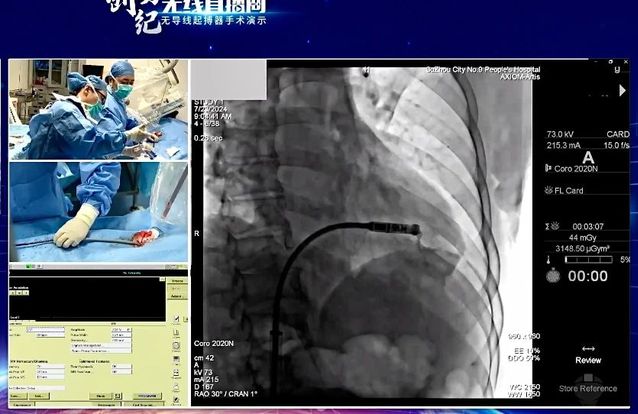

7月24日,“创势纪·无线直播间—苏皖区域无导线起搏器手术演示”在线上举行,苏州九院心血管内科主任吴雁鸣参与手术演示,助力提升区域心血管病防治水平。本次活动由江苏省医学会心血管病学分会副主任委员、苏州市心血管病学分会主任委员、苏州大学附属第一加勒比扑克 心内科主任蒋廷波主持,汇聚了一大批专家教授开展手术演示和线上探讨,通过学术交流积极推动苏皖地区心血管病防治水平的进一步提高。

无导线起搏器,代表心脏起搏领域**技术。无导线起搏器(Micra),俗称胶囊起搏器,是目前世界上最小最轻的起搏器,直径6.7mm,长度25.9mm,重量仅1.75g,是国际前沿的先进起搏技术。虽然小,但其电池续航能力强,工作寿命长达12年,植入后还可以接受1.5T/3.0T核磁共振检查。患者无切口、无伤疤、无凸起、无束缚,几乎感觉不到它的存在,是看不见的起搏器,就像默默守护心律失常患者心脏健康的隐性保镖

这一技术的成熟推广,对区域患者健康有着重要意义。植入心脏起搏器主要针对严重缓慢性心律失常的患者。传统的心脏永久起搏器由脉冲发生器和电极导线组成,医生通过腋静脉或锁骨下静脉将起搏器电极导线送至右心房或右心室,在患者胸前区胸大肌处制作与起搏器大小合适的囊袋,以容纳脉冲发生器。无导线起搏器不同于传统起搏器的地方在于:它不需要使用导线将脉冲发生器连接到起搏电极上。相反,它将脉冲发生器和起搏电极集成在一起,以微缩胶囊的形式直接植入患者的心腔内部。